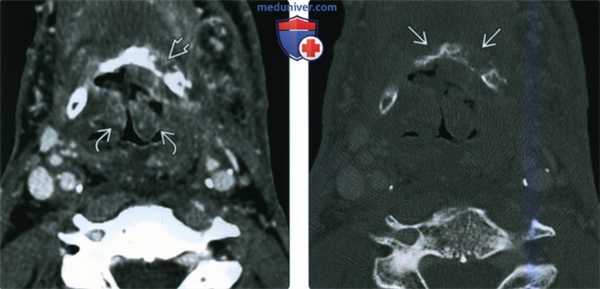

(Слева) КТ с КУ, аксиальная проекция. Пациент после курса лучевой терапии по поводу плоскоклеточного рака надсвязочного отдела гортани. Имеется выраженный отек обеих черпалонадгортанных складок, ведущий к выраженному сужению дыхательных путей. Подъязычная кость выглядит фрагментированной, что является признаком остеораднекроза или опухолевой эрозии. Солидных мягкотканных образований поблизости не имеется.

(Справа) КТ в костном окне, аксиальная проекция, тот же пациент. Деструкция подъязычной кости определяется более четко. Оказалось, что ее причиной является остеораднекроз, достаточно редкая форма радионекроза гортани.